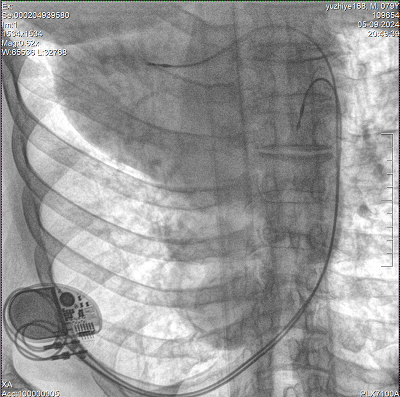

具備血管造影及數(shù)字減影(DSA)、路徑圖(Road-map)、透視、攝影等功能。 廣泛適用于介入科、血管外科、腫瘤科、消化內(nèi)科及骨科等多個(gè)臨床科室,典型應(yīng)用包括:TACE(肝腫瘤栓塞與化療灌注術(shù))、心臟起搏器置入術(shù)、四肢動(dòng)脈造影術(shù)、下肢靜脈濾器置入術(shù)、ERCP(經(jīng)內(nèi)鏡逆行胰膽管造影術(shù))等。

核心DSA軟件可實(shí)時(shí)生成高清血管影像,結(jié)合路徑圖功能,在手術(shù)中為醫(yī)生提供血管導(dǎo)航。

設(shè)備搭載自主研發(fā)的大功率高壓發(fā)生器、高熱容球管與大尺寸平板探測(cè)器,配合先進(jìn)圖像處理算法及高效冷卻循環(huán)系統(tǒng),能夠在長(zhǎng)時(shí)間手術(shù)過(guò)程中持續(xù)輸出高清圖像并保持幀率穩(wěn)定。